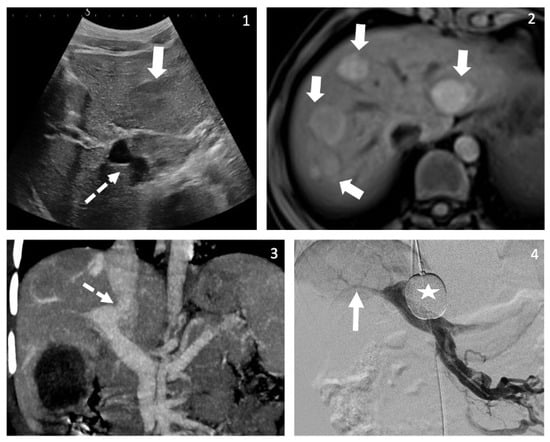

2.1. Case A

| A | Suspected PAH | 9 | 11 | Dyspnea | Beta-catenin mutated adenomas | Insulin resistance with hyperinsulinism, acanthosis nigricans and hyperandrogenemia without menarche |